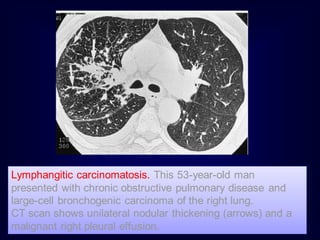

Lymphangitic carcinomatosis. This 53-year-old man

presented with chronic obstructive pulmonary disease and

large-cell bronchogenic carcinoma of the right lung.

CT scan shows unilateral nodular thickening (arrows) and a

malignant right pleural effusion.

Lymphangitic carcinomatosis. This53-year-old man presented with chronic obstructive pulmonary disease and large-cell bronchogenic carcinoma of the right lung. CT scan shows unilateral nodular thickening (arrows) and a malignant right pleural effusion.